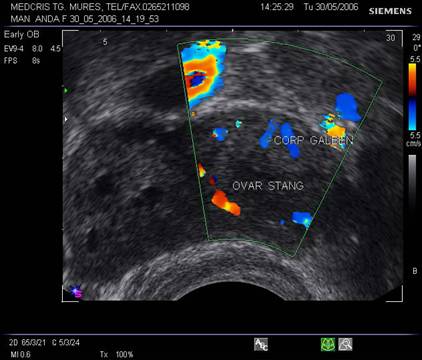

11.sarcina si Tumorile anexiale

Cea mai frecventa formatiune anexiala este corpul galben fiziologic. El apare ca o umbra bine circumscrisa, anecogena initial, apoi formatiunea adiacenta uterului regreseaza, spre deosebire de alte formatiuni chistice ovariene. Regresia schimba aspectul ecografic spre o formatiune inomogena cu ecou anecogen central.[4,8]

Tumorile anexiale maligne sunt foarte rare, una la 18000 - 25000 sarcini. [5,13] Suspiciunea ecografica se pune pe modificarile peretelui chistic cu proliferare papilara, iar Dopplerul color indica flux sanguin bine reprezentat si cu indici scazuti de rezistenta.Tumorile anexiale trebuie diferentiate de cele ale altor organe - intestin subtire, sigma, colon, rinichi pelvin ectopic, etc.

Fig. nr. 94. Corp galben gestational